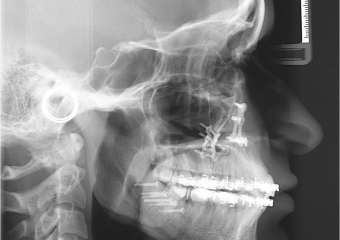

Telerradiografia inicial